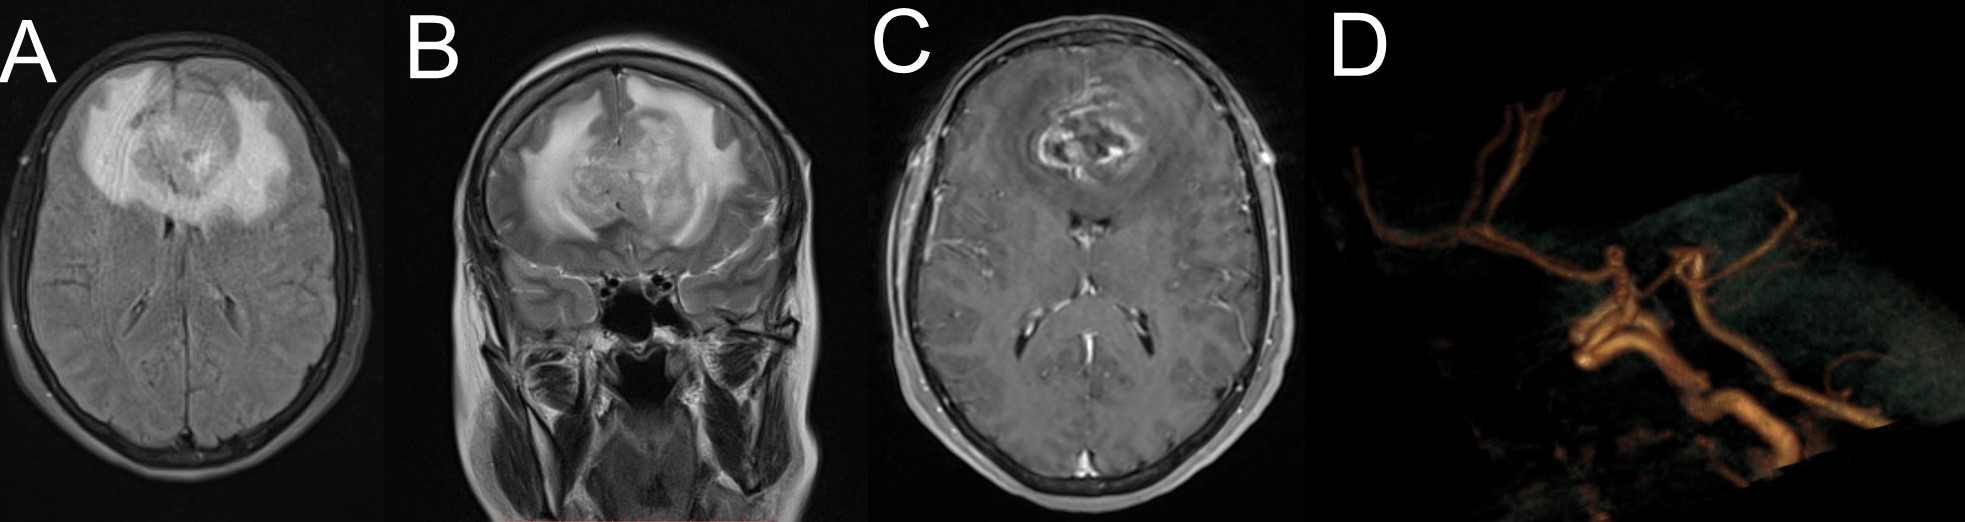

Tratamiento microquirúrgico de tumores cerebrales